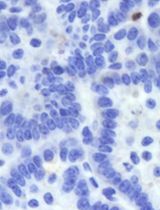

To take a snapshot: highlight one of the control wells and a single field of view. Then, within the Channel Selection window, click Snapshot in any of the channels to take one image to check if the leukemia cells are in focus. If cells are not in focus, change the heights for AO, PI, and Brightfield channels until the cells are in focus (Figure 3).

Figure 3. Overlay of primary patient leukemia cells and mesenchymal stromal cells (MSCs) stained with acridine orange/propidium iodide (AO/PI) for calculating percent cell viability. White arrows indicate MSCs, red arrows indicate dying leukemia cells, and yellow arrows indicate live leukemia cells.